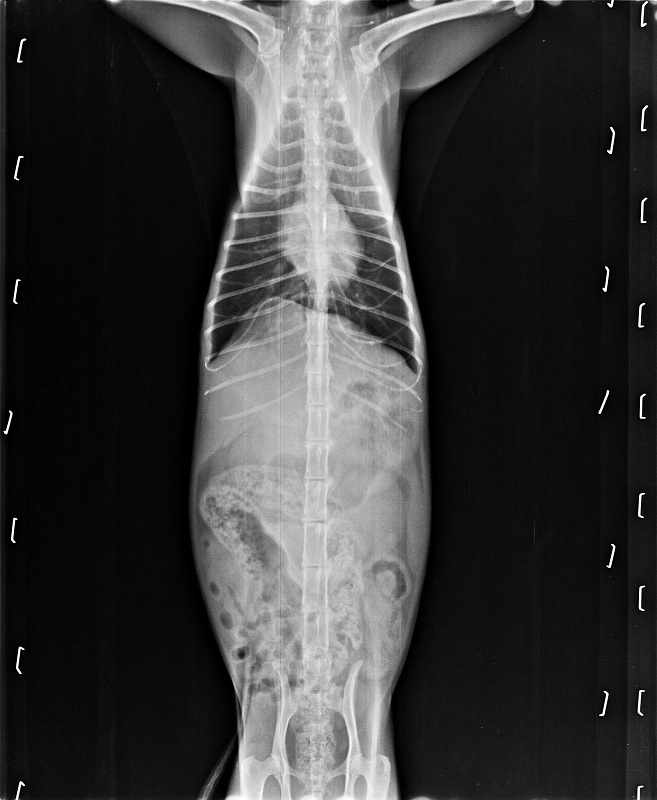

主題: 因脫水耗弱、口腔嚴重發炎,且有鼻膿分泌物的盈盈 申請者姓名: 臺北市支持流浪貓絕育計劃協會 花色: 申請日期: 2017-11-01 12:19:19 申請者部落格: 申請者臉書網址: 所在縣市/合作醫院: 台北市/極光動物醫院 治療費用: 22599元 需求人數: 50人 已結案 (2024-06-01 13:20:53) 報名人員: Nina Chiu(已付款)、Mimi Liu x2(已付款)、Nicole Chen x2(已付款)、yuling(已付款)、Wanting(已付款)、Naommi x2、姿馬麻、Noel6731(已付款)、Amanda Ke(已付款)、阿奇拉 x2(已付款)、Helen Yu(已付款)、張香香、Me I Me I liao x2(已付款)、貓兩拳(已付款)、陳金鳳 x2(已付款)、wgs(已付款)、Arthur Nana(已付款)、Stiff(已付款)、May x4(已付款)、林嘉南(已付款)、Naommi x2(已付款)、Sophia Kuo(已付款)、JUN x2(已付款)、接小力 x2(已付款)、devin(已付款)、陳亮尋 x5(已付款)、塔羅小蘋與客人們(已付款)、小橘子(已付款)、瀅瀅(已付款)、Wi Chen(已付款)、Fatefaye Wu(已付款)、小珍 x2(已付款)、白婷 x2(已付款)、Guan-Yi Li(已付款)、洪凱威 x2(已付款)、 候補人員: 動物病情說明: 8/16~8/30盈盈住院

盈盈因食慾不佳及上呼吸道膿樣分泌物,

於106年8月16日就診。

經醫師檢查發現,盈盈可能歷經全口拔牙,口腔呈現嚴重發炎,並有多數傷口癒合不良之情形

而血液檢查有肝指數上升與貧血之症狀。

合併上呼吸道感染等多數原因,

推斷是造成盈盈無法自行進食、脫水與身體耗弱等之情況。除給予必要點滴維持、抗生素治療與灌食照顧外,

也須同時配合持續性密切的生理數值監測,

因此建議繼續在醫院治療直至穩定出院為止。

動物近況說明: 原先以全口拔為拔乾淨導致持續發炎的盈盈

已經再次接受清除殘留齒根的手術

目前狀況良好